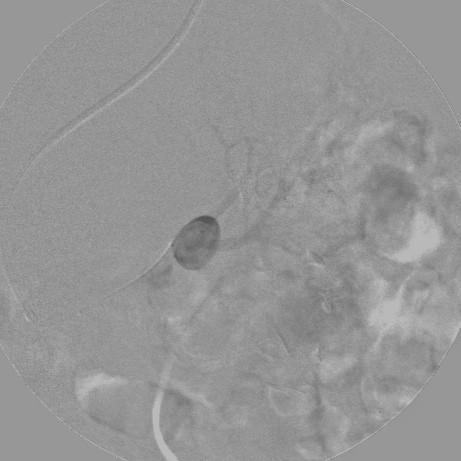

We describe the successful use of a new neurointerventional coil to treat an enlarging wide-necked segmental-branch renal aneurysm in an elderly woman who was not a candidate for surgery because of several comorbidities.

The technique described allowed safe, successful treatment of a wide-necked aneurysm in an unfavorable vascular territory, reducing the risk of downstream artery embolization and consequent parenchymal damage and decreased renal function. In similar cases, other endovascular devices have often proven to be ineffective at nephron sparing. To validate the safety and efficacy of this system, more cases treated in this manner should be studied.